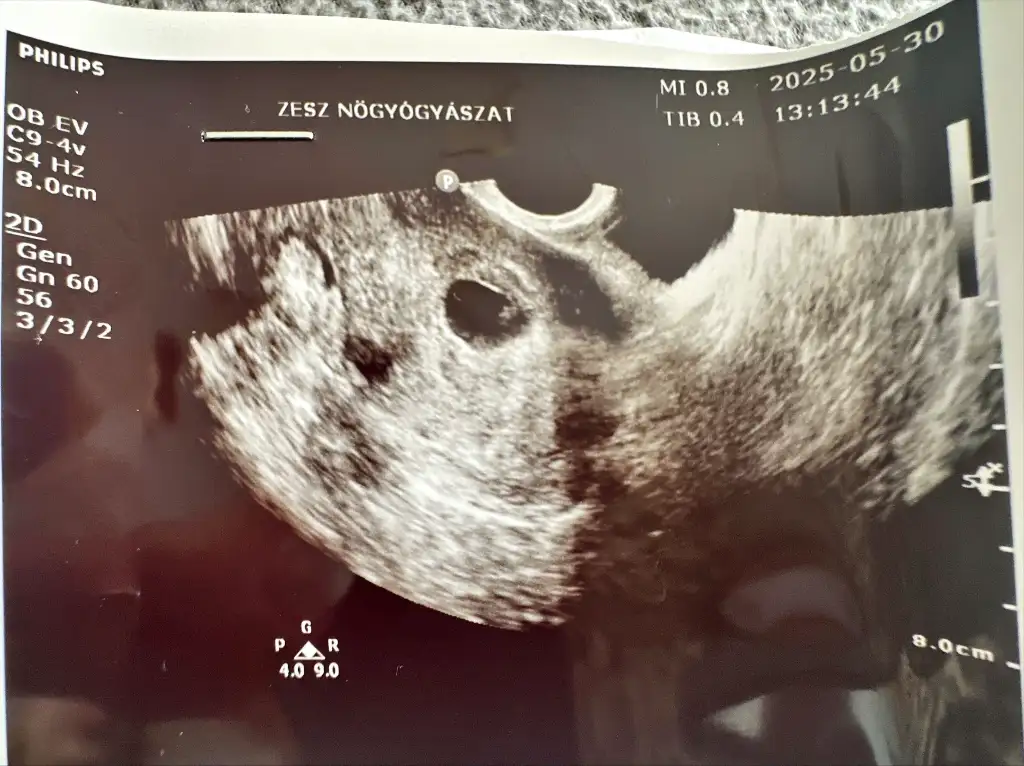

Embryo ilk gördüğümüzde maalesef devlet hastanesi doktoru hiç bi ölçüm yapmadı (ben ultrason görseline bakınca tahmini 18-20mm olduğunu düşünüyorum canım) söylediğim halde ben de doktor değiştirdim sonraki randevuda. Ozaman tarih Mayıs 30 idi hatta fotosunu buraya koydum.Qyyy ne güzel maşallahne zaman gördünüz peki son muayenede mi kese boyu tam kaçtı gördüğünüzde

Amin rabbim nasip etsin inşallah hepimize .. malesef bu tarz doktorlar yüzünden sevincini yaşayamadan endişesine kapılıyor insanEmbryo ilk gördüğümüzde maalesef devlet hastanesi doktoru hiç bi ölçüm yapmadı (ben ultrason görseline bakınca tahmini 18-20mm olduğunu düşünüyorum canım) söylediğim halde ben de doktor değiştirdim sonraki randevuda. Ozaman tarih Mayıs 30 idi hatta fotosunu buraya koydum.

Hepimiz tokat yemişiz bazı doktorlardan valla. Ama endişe etmeyin kızlar akışına bırakmayı öğrenmemiz lazım.Embryo ilk gördüğümüzde maalesef devlet hastanesi doktoru hiç bi ölçüm yapmadı (ben ultrason görseline bakınca tahmini 18-20mm olduğunu düşünüyorum canım) söylediğim halde ben de doktor değiştirdim sonraki randevuda. Ozaman tarih Mayıs 30 idi hatta fotosunu buraya koydum.